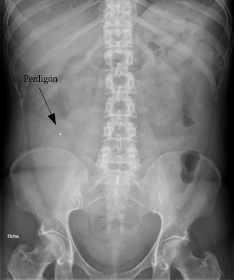

La radiografía simple del abdomen solamente me mostraba un perdigón

¡Pero que demonios! Eso solamente significa que a la paciente le gusta comer carne de caza y antes alguien no limpió bien la carne de perdigones.